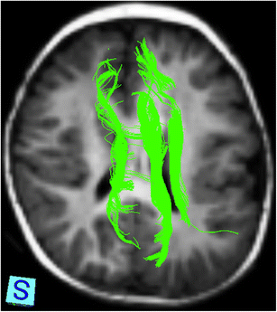

Diffusion tensor imaging (DTI) is an advanced MR technique that provides qualitative and quantitative information about the micro-architecture of white matter. DTI and its post-processing tool fiber tractography (FT) have been increasingly used in the last decade to investigate the microstructural neuroarchitecture of brain malformations. This article aims to review the use of DTI and FT in the evaluation of a variety of common, well-described brain malformations, in particular by pointing out the additional information that DTI and FT renders compared with conventional MR sequences. In addition, the relevant existing literature is summarized.